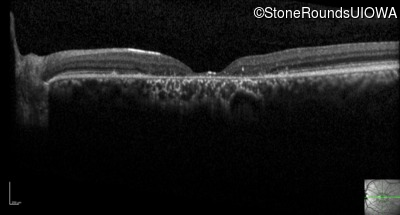

Optical Coherence Tomography - Right - 20/100 +1

Exemplar / OCT Stack

OCT Stack